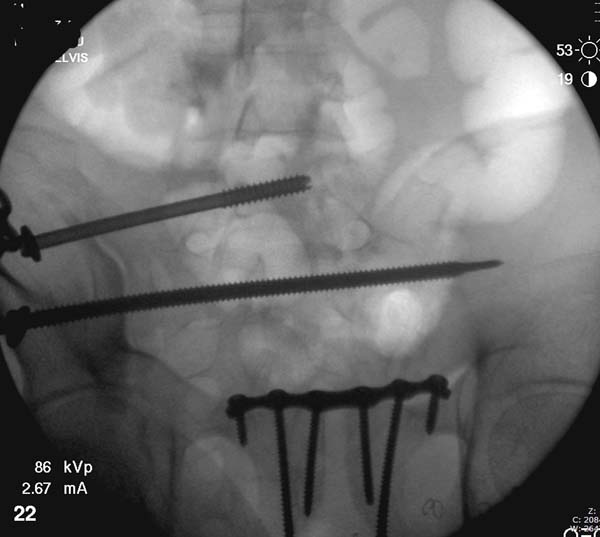

Перелом заднего отдела крыла подвдошной кости доказывает, что задние связочные элементы подвздошно- крестцового сочленения интактны, и такой перелом известен как “Сrescent fracture’. Переломы разделяется на 4 типа, и до фиксации надо хорошо изучить топографию перелома, иначе винт может попасть в линию перелома и не удержать фиксацию.

Но вам повезло, двумя винтами смогли зацепить и репонировать переломо-вывих. Обычно такие переломы надо фиксировать спереди или сзади пластиной или шурупом, т.е. создать дополнительную стабильность крыла, кроме перкутанной фиксации.

Здесь примеры фиксации с различными вариантами.... .